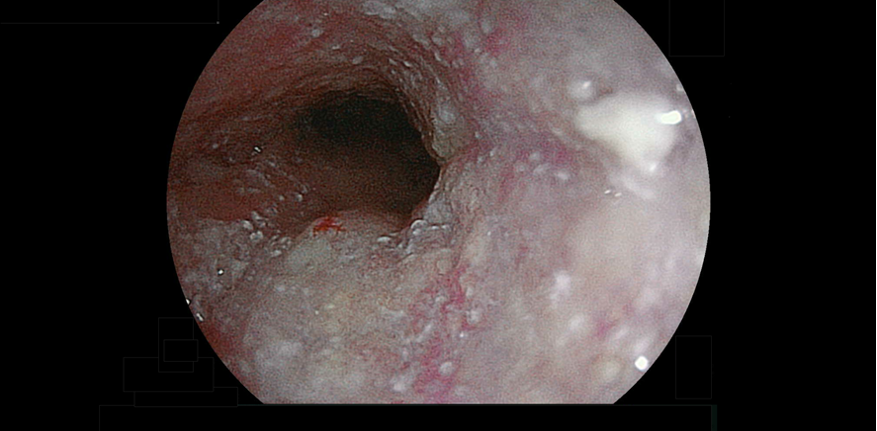

強い酸性の胃液(胃酸)が胃の内容物とともに食道に逆流し、食道の粘膜に炎症が生じる病気です。胃酸が増えすぎてしまったり、胃酸の逆流を防ぐ機能がうまく働かなかったりすることで起こります。胃酸がのどまで上がってきて酸っぱいと感じるようになったり、胸やけやのどがヒリヒリしたりして不快感が続きます。喫煙、飲酒などの生活習慣や加齢、肥満、姿勢、食道裂孔ヘルニアなどが原因となります。